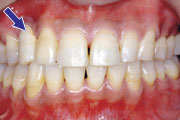

症例3

43歳女性です。前歯の虫歯治療を希望して来院されました。歯肉の腫れが著しく、ブラッシング時には必ず出血するとのことでした。精密検査をして治療計画を立案した上で、患者さんの希望を伺い最終的な方針を決定し、歯周病治療と審美的歯周病治療をせずに、審美治療だけを行うと、将来治したはずの歯がグラグラしたり、歯茎が下がって、美しくかぶせたはずのセラミック冠の根元が見えてくるほどの不都合が生じてきます。